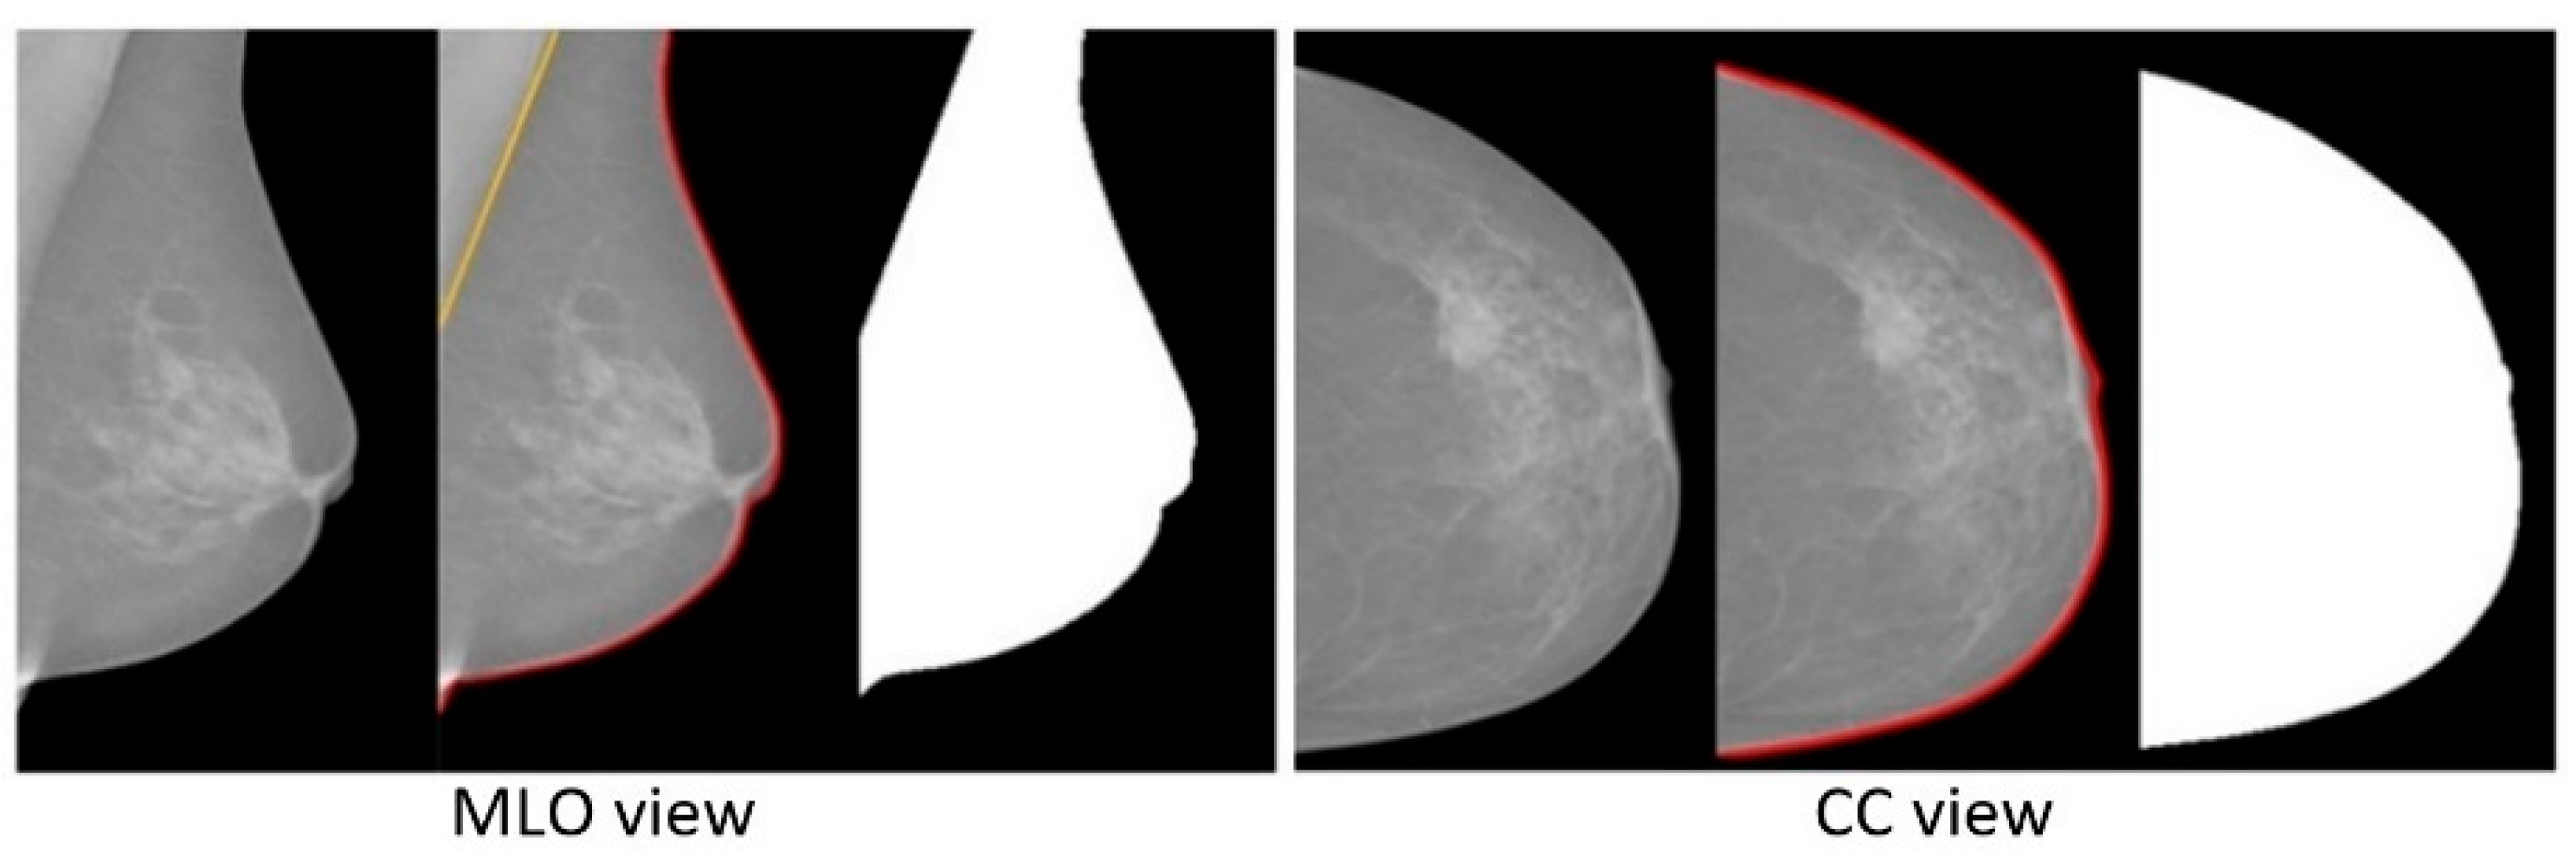

This pre-processing step contains breast area segmentation, denoising operation, and resizing the image. Breast segmentation is first applied to remove nonbreast areas such as background region, pectoral muscle, and label artefacts. A multifractal-method-based feature-enhanced image [30] is used to highlight the contrast between image background and the breast tissue region. The intensity thresholding method and morphological operations [31] are used to separate breast region and artefacts from the background. The label artefacts can be removed by keeping only the largest connected area (breast region). K-means algorithm and polynomial fitting approach [32] are employed to eliminate pectoral muscle from the breast region in MLO view mammograms. A median filter of 3 × 3 size is used to reduce noise. Finally, mask images are obtained, which are used to extract image features only from the region of interest (breast area) in the following steps. As relative work [16,17] reported promising classification results using resized mammogram images, this study applies the bicubic interpolation method to resize processed images with a scale factor s [33], resulting in a resized image that is s times the size of original image. Figure 3 and Figure 4 show some examples of segmenting breast region from image background using INbreast and MIAS mammograms, respectively. For the MIAS dataset that only contains MLO view images, relative work [21,34] demonstrated that using a cropped square region of interest (ROI) produces a better classification result. This study therefore uses a similar method as that in [34] to obtain the ROIs in MIAS. Figure 5 illustrates ROI extraction in MIAS mammograms. A detailed introduction of this pre-processing stage can be found in Supplementary Materials.

Figure 3.

Examples of segmenting breast region and removing pectoral muscle area in INbreast mammograms.

Figure 4.

Segmentation of breast region in MIAS mammograms: (a) input mammogram, (b) enhancing breast region and artefact areas, (c) rough contour of breast region, (d) smoothing breast contour, (e) finding pectoral muscle area, (f) breast mask image without pectoral muscle region.